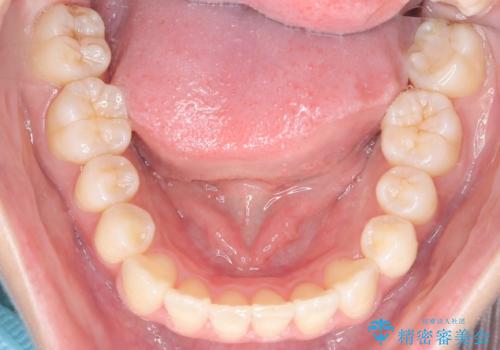

前歯の叢生・Ⅱ級咬合を改善|TADを用いた遠心移動+インビザライン矯正

前歯部の叢生(ガタガタ)と臼歯関係のズレを改善するため、抜歯をせずに奥歯を後方へ移動(遠心移動)させることを選択しました。TADという小型のアンカースクリューを顎骨に設置することで、確実かつ効率的に奥歯を後方へ移動させました。併せて透明で目立ちにくいインビザラインを用いることで、審美性を保ちながら治療を進めることが可能でした。患者様の負担が少ないマウスピース矯正と固定源のTADを組み合わせることで、抜歯することなく歯並びと噛み合わせを大幅に改善でき、大変ご満足いただけました。